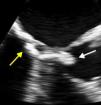

A 79-year-old woman was referred to our department because of suspected angina. The electrocardiogram showed ventricular repolarization abnormalities in the lateral wall. Transthoracic echocardiography showed preserved biventricular systolic function, without wall motion abnormalities, a mitral valve with normal functional area and marked calcification of the annulus, and on the ventricular side a hyperechoic, threadlike and highly mobile mass, protruding into the left ventricular outflow tract, causing a dynamic gradient of 24 mmHg (Video 1). Transesophageal echocardiography (TEE) showed a mass adjacent to the posterior annulus of the mitral valve, measuring about 25 mm×5 mm (Figure 1; Video 2 and 3). Computed tomography confirmed a large calcified mass attached to the ventricular side of the mitral valve (Figure 2). No mass was observed on cardiac magnetic resonance imaging, probably due to its marked mobility. Myocardial perfusion scintigraphy showed evidence of inferolateral ischemia and cardiac catheterization revealed left main and three-vessel disease. Bypass surgery was performed and the intraventricular tumor was removed (Figure 3). Histology confirmed the diagnosis of calcified amorphous tumor (Figure 4).